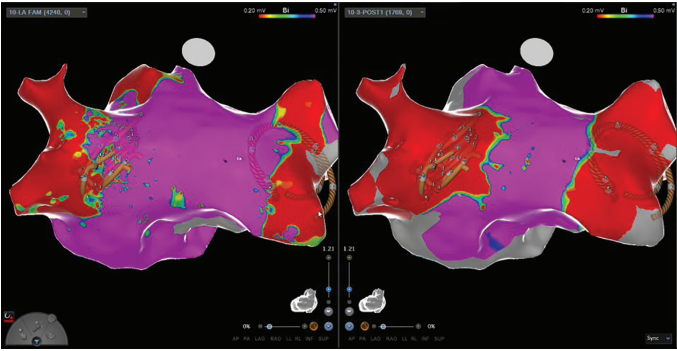

The recent implementation of pulsed field ablation (PFA) technology at Dignity Health (Figure 2) has significantly reduced procedure times, enhancing both efficiency and patient outcomes. PFA is a novel, nonthermal ablation technique that uses high-voltage electrical pulses to create irreversible electroporation, disrupting myocardial cell membranes while sparing surrounding tissue.8 Studies have demonstrated PFA’s outstanding efficacy and safety in achieving pulmonary vein isolation with a 0% risk of esophageal injury and phrenic nerve damage compared to the 40%-60% risk of esophageal injury and the 4.2% incidence of phrenic nerve injury associated with cryoablation (CA) and radiofrequency ablation (RFA).9,10 However, recent meta-analysis of 1199 patients showed no significant difference in periprocedural complications or arrhythmia recurrence when comparing PFA to CA and RFA.11 PFA procedures have a median duration of approximately 61 minutes, significantly shorter than traditional methods like RFA (median 171 minutes) and CA (median 84 minutes).12 The reduction in procedure time also decreases the duration of anesthesia, thereby reducing potential anesthesia-related complications that could delay SDD.